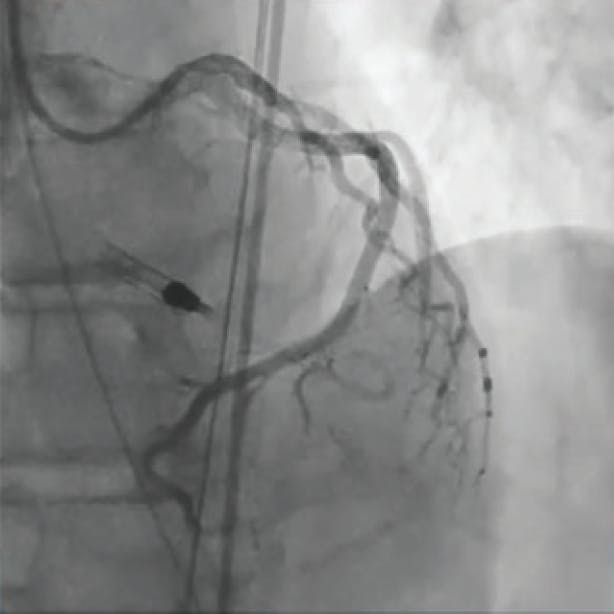

A 2-mm balloon was used to perform the Dotter technique to predilate the vessel (Figure 1). Heavy thrombus burden was visualized angiographically, and it was decided that mechanical thrombectomy with CAT RX would be introduced (Figure 2). After multiple passes of CAT RX with 30 seconds of aspiration each, there was improved flow through the vessel (Figure 3). Then, 4- X 38-mm and 4- X 32-mm drug-eluting stents (DESs) were placed distally and in the midbody, resulting in thrombolysis in myocardial infarction (TIMI) 3 flow (Figure 4).

Figure 3. Improved flow through the vessel after using CAT RX.

Figure 4. TIMI 3 flow achieved.